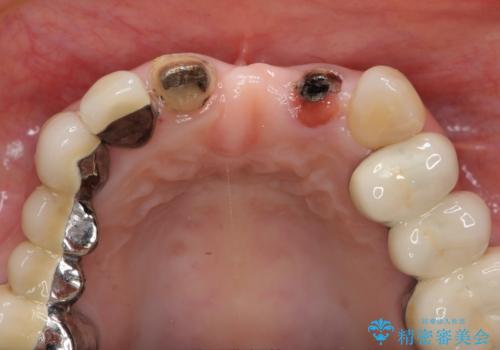

- 前歯の審美障害、見た目の改善を希望され来院されました。

歯肉縁下カリエスも認められるため、挺出を行いセラミックブリッジを審美的に新製します。